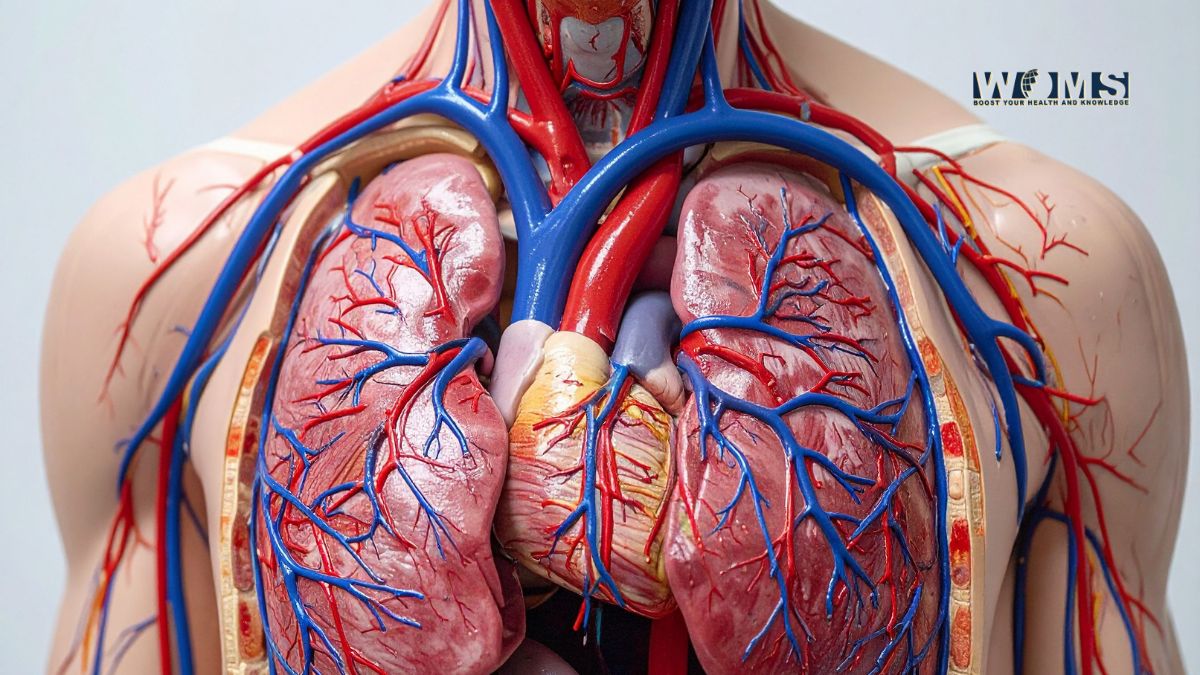

Location of the vertebral artery

The vertebral artery is found in the upper part of the neck. It runs through the spine and branches out into many different arteries. Since it is a large blood vessel, many valves help to prevent it from becoming blocked or impeded.

The extent of the vertebral artery

The vertebral artery terminates between T1-2 in front of the medulla oblongata, where it bifurcates into two branches that run to either side of the brainstem. These arteries then subdivide into branches supplying blood to different regions; these smaller arteries are called anterior spinal, posterior spinal, and craniocervical arterial trunks.

What are some important landmarks on the vertebral artery?

The vertebral artery is a major artery that runs along the spine. It begins near the base of the skull and extends down to the tailbone, branching into two large arteries just before it passes through each side of the spinal cord.

What is the function of the vertebral artery?

The vertebral artery carries blood to the brain and spinal cord base, which are vital structures that make up much of the central nervous system. It is one of the two terminal branches of the subclavian artery and arises opposite the cervical vertebrae at C6-7. The subclavian arteries are located under collarbones and give birth to different arteries throughout their journey toward their terminus at C1-2, where they bifurcate into left and right common carotid arteries.

Which portion of our spine does it service?

The spinal cord. It’s the lifeline of our nervous system, supplying messages to and from various parts of our body. The vertebrae are the bones that protect this delicate nerve bundle, which is about three and a half inches long and located in the middle of your back. It sits behind your neck, at the base of the skull.

How does it provide blood flow to the brain?

The vertebral artery is a large artery that supplies blood to the head, neck, and upper trunk. It is one of the two terminal branches of the subclavian artery and arises opposite the cervical vertebrae at C6-7. The subclavian arteries are located under collarbones and give birth to different arteries throughout their journey toward their terminus at C1-2, where they bifurcate into left and right common carotid arteries.